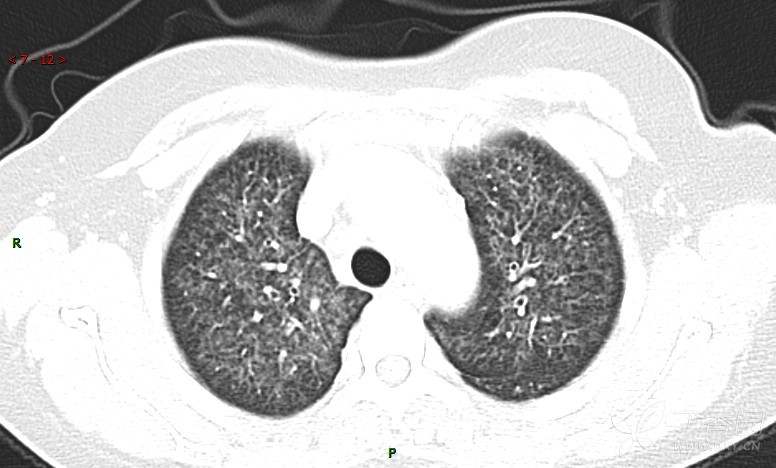

肺内弥漫性网状结节影,PET-CT却无阳性病灶,这是?(附其他2例链接)

女性,58岁,阵发性咳嗽2月,加重1月。

患者于2月前无明显诱因出现咳嗽,以阵发性干咳为主,接触冷空气后咳嗽明显,偶咳少量白色泡沫样痰,咳嗽剧烈时感憋喘,无发热、盗汗,无头痛、头晕,无胸痛、咯血,无恶心、呕吐,无腹痛、腹泻,无尿频、尿痛等不适,于当地医院给予肌注及静脉药物治疗,具体药物名称不详,效果欠佳,近1月来患者咳嗽频率较前增加,咳嗽剧烈时感双侧季肋区疼痛不适,10余天前出现发热,体温在38℃左右,伴畏寒、寒战,无头痛、头晕,无纳差、乏力等不适,药物治疗后体温降至正常,仍阵发性咳嗽,今为求进一步诊治,就诊于我院急诊,因呼吸内科暂无床位,急诊门诊以“肺间质病变”收入急诊留观室,给予“抗感染、止咳”等对症支持治疗后,今日以“肺间质性病变”收入我科,患者自本次发病以来,神志清,精神可,饮食尚可,睡眠一般,大小便正常,体重较前无明显变化。

患者活检肺组织后行PET/CT检查